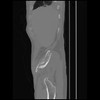

7 CUERPO,CE,Sagittal,3.000,CUERPO,Sagittal,